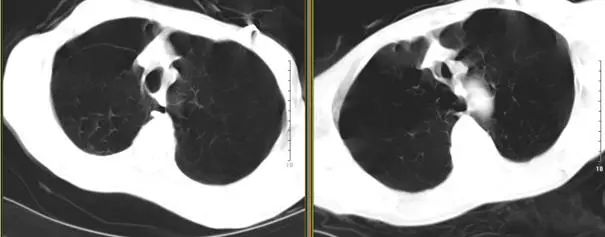

高分辨胸部CT提示:肺气肿以双肺上叶为著,右肺上叶肺大疱,中叶呈外压性条索状,右侧斜裂完整。

术后3天复查胸部平片(图6)提示:右肺容积较前减少,纵隔右移,膈肌穹顶较前提高。

术后5天胸部CT(图7)显示右肺上叶局灶性气胸,肺大疱明显缩小,中叶未能复张,血气分析(鼻导管吸氧2L/min)提示:PH 7.425,PaO261.8 mmHg,PaCO246.8 mmHg,HCO3 -30.0 mmol/L,遂出院观察。住院期间无院内获得性肺炎、咯血、单向活瓣移位等并发症。

图7 术前2天(右)与术后5天(左)胸部CT对比